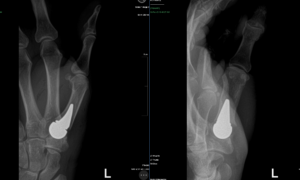

Finger Reattachment Surgery (4 Finger Amputation With A Circular Saw)

JJ is a delightful and vigorous 73 year old retired man whose favorite hobby is making Westminster chimes clocks for his grandchildren. One ordinary day when he was using a circular saw to cut the molding for another clock, he sustained a devastating injury. He amputated the four fingers of his left hand and was… [Read More]